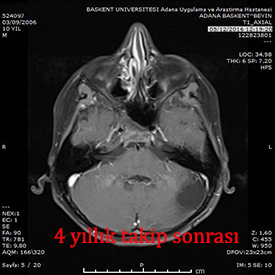

7 yaşında çocuk baş ağrısı ile geldi. yapılan incelemlerde beyincik ile beyin sapı arasında, 4.ventrikül dediğimiz beyin sıvısının dolaştığı odacığı tıkamış kitle tespit edildi. Başarılı bir ameliyat ile kitle tamamen çıkarıldı. Patoloji sonucu Ependimom (2.derece) geldi. Sonrasında radtoterapi aldı. 3,5 yıldır takipte olan hasta sağlıklı ve beyin filmlerinde hiçbir tümör bulgusu yok.